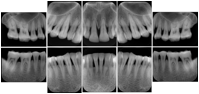

2. A patient requests cosmetic surgery to enhance their facial appearance. The case requires consultation between an orthodontist in New York and an oral surgeon in California. The cephalometric series of 2D projections constructed from a volumetric CT data set that is used for the discussion is arranged by a Structured Display for transfer between the two practitioners.

Cephalometric Series Structured Display

Figure OO-2. Cephalometric Series Structured Display